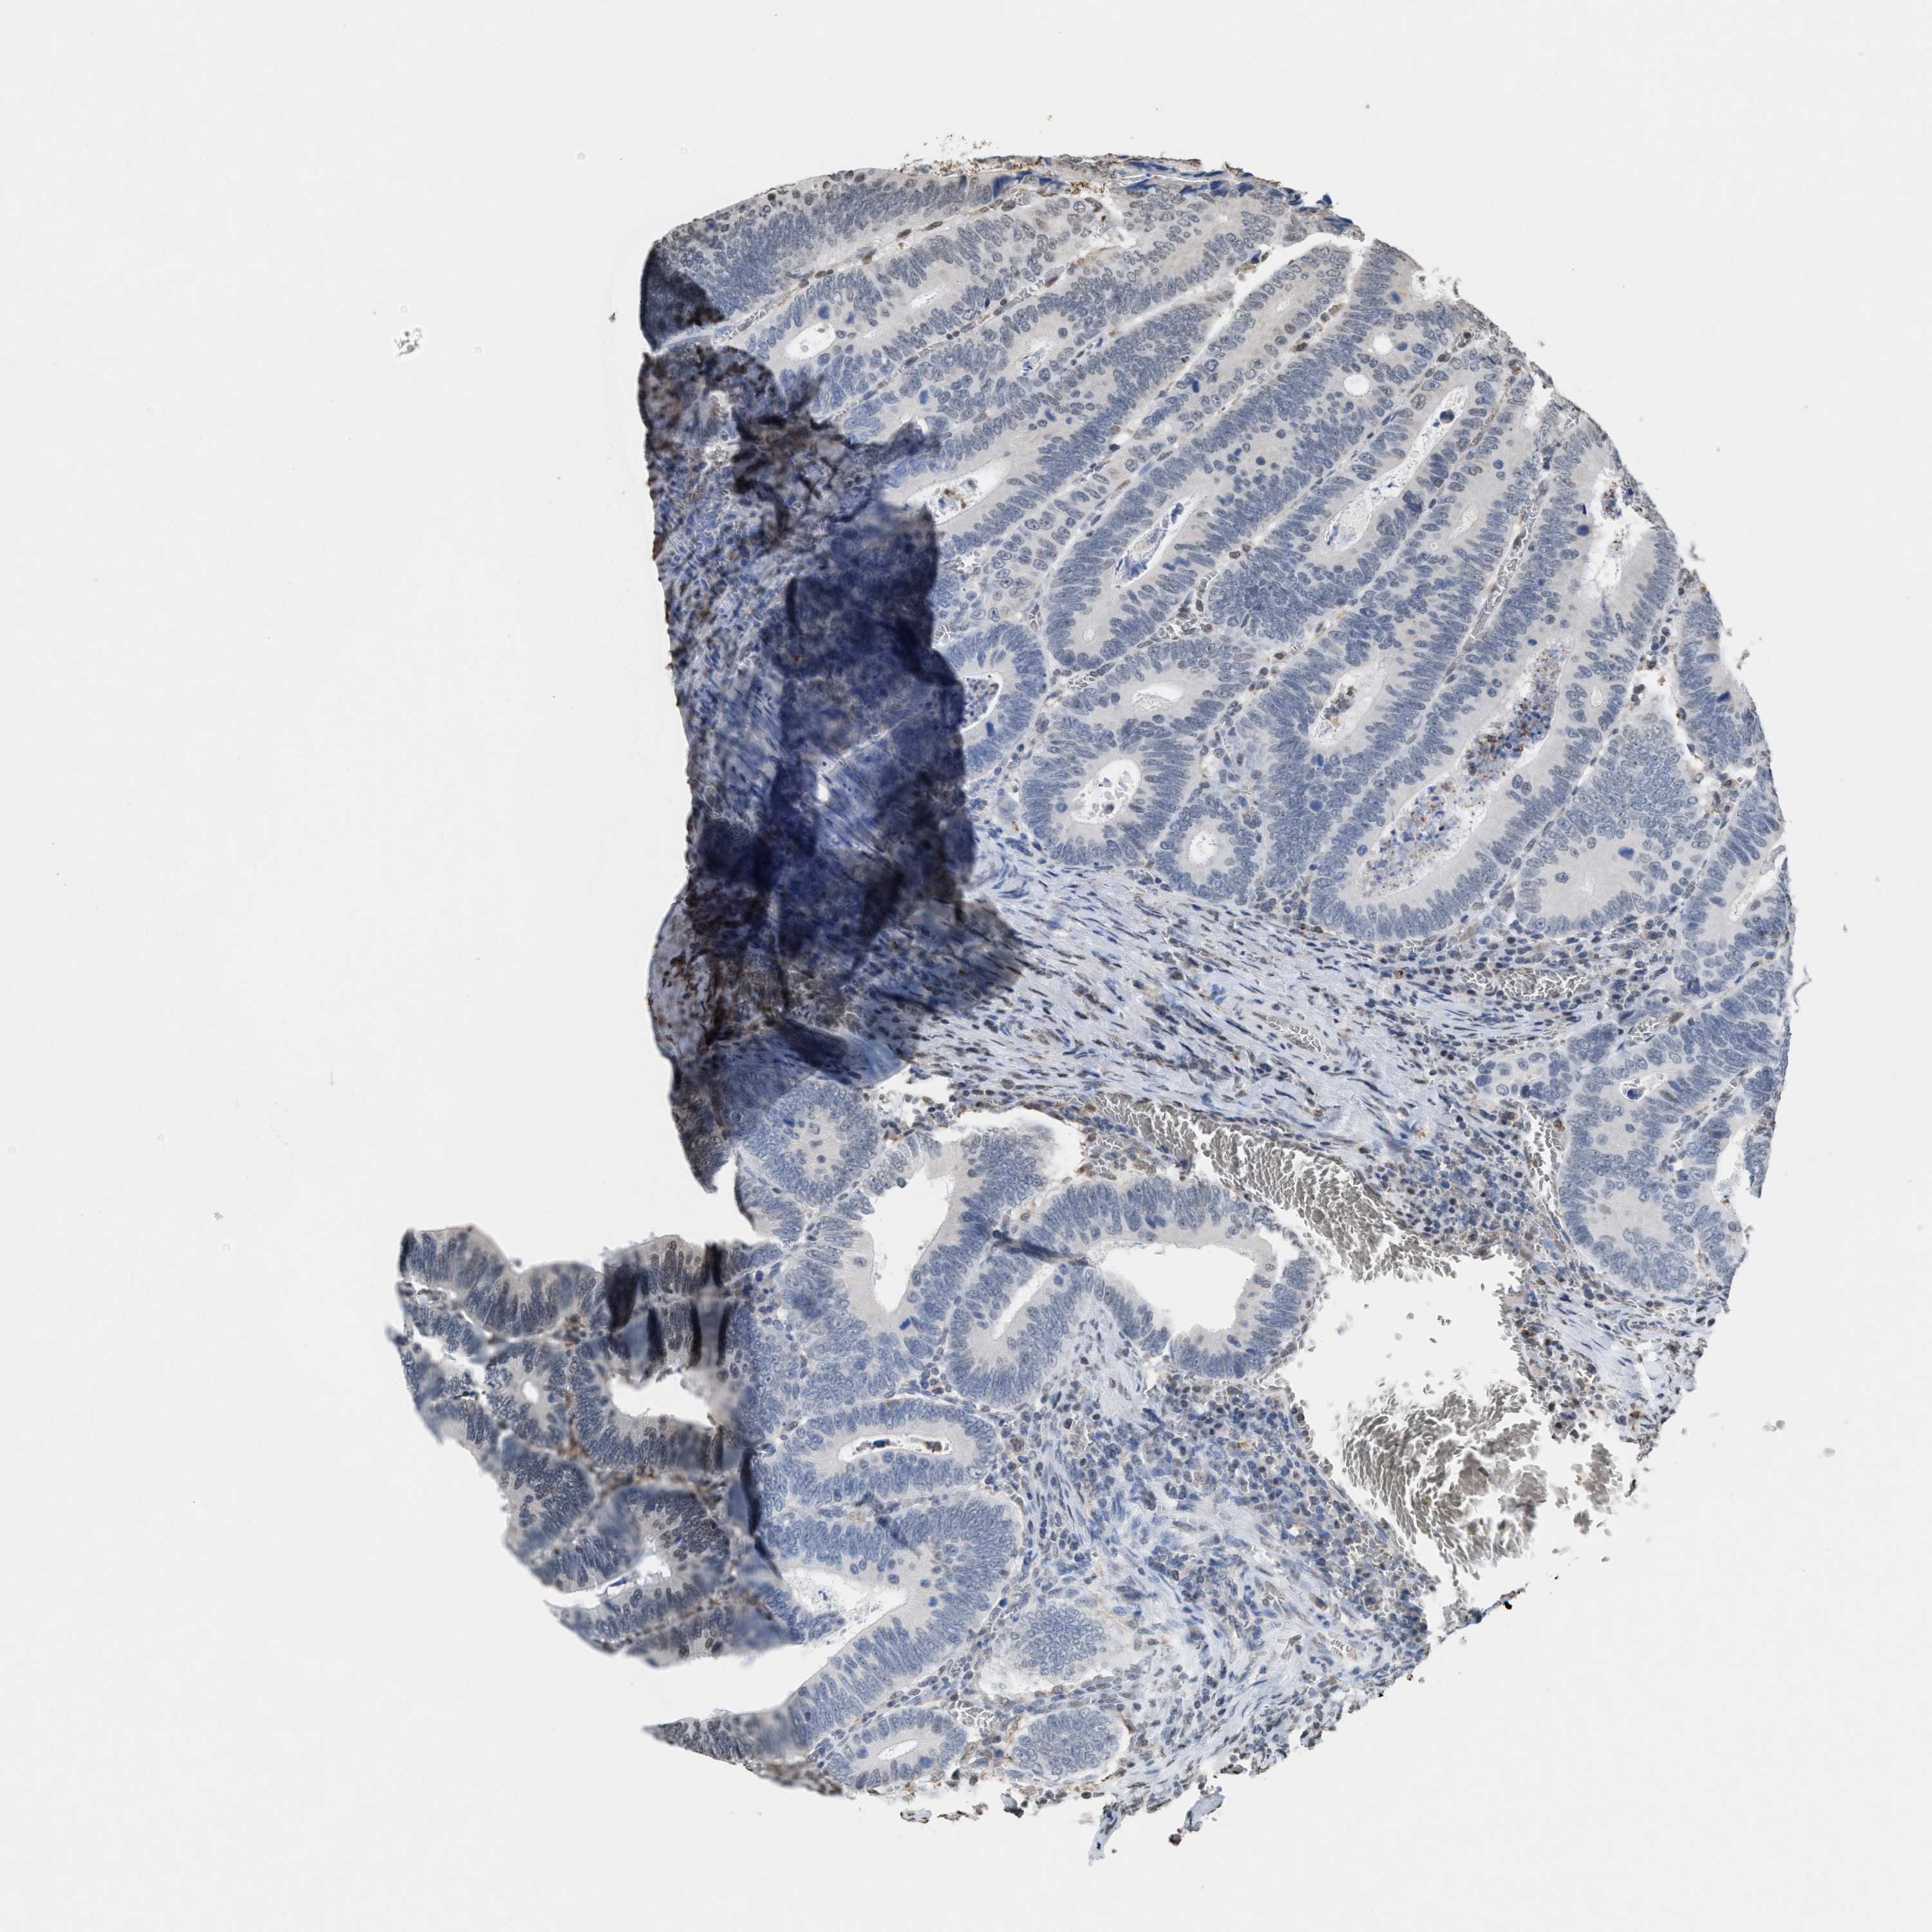

CANCER COLORECTAL CANCER Show tissue menu

Colorectal cancer

Human cancer

Colon adenocarcinoma